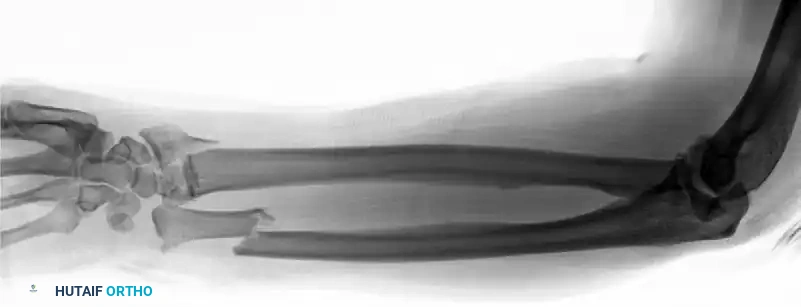

Figure 57-82A: Preoperative AP radiograph of a displaced both-bone forearm fracture in an adult.

Figure 57-82B: Preoperative lateral radiograph demonstrating significant translation and loss of the radial bow.